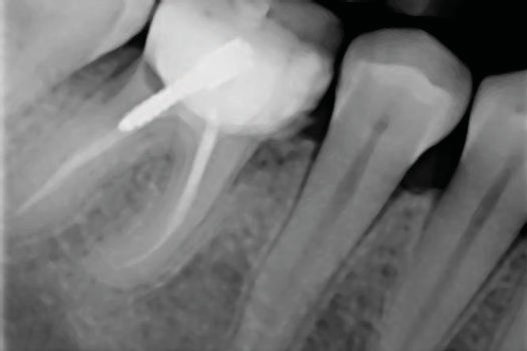

- Причинами удаления зубов были неудачи эндодонтического лечения, прогрессирующий кариес и разрушения (рис.1 и 2);

Рис.1в. Нереставрируемый первый большой кореной зуб нижней челюсти. (a) Исходная клиническая картина; (б) периапикальная рентгенограмма; (в) окклюзионный вид, показывающий мезиодистальное разрушение.